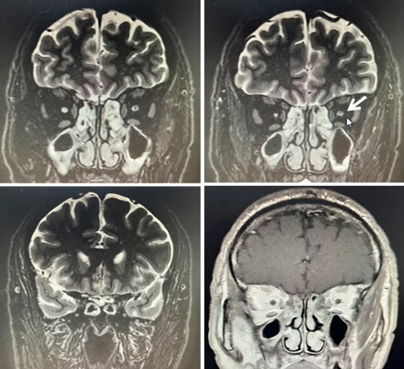

• 视神经MRI:右侧视神经眶内段至颅内段变细、信号增高。左侧视神经眶内段变细、信号增高,无强化。

• 颅脑MRI:左侧基底节区腔隙灶不除外,双侧上颌窦黏膜增厚。